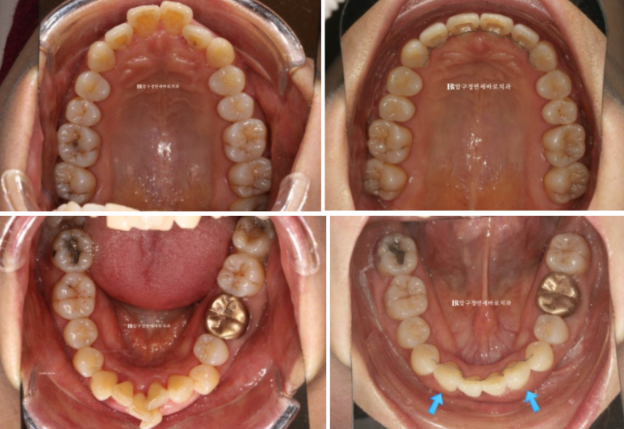

파란 화살표는 송곳니이고 앞니 자리로 잘 이동했습니다.

파란 화살표 앞니 자리에 와 있는 송곳니입니다.

앞니쪽 치주염은 꾸준히 관리로 잘 치료가 되었고 앞니 뻗침은 개선이 되었습니다.

2022.11~24.05

앞니 4개가 있어야 할 자리에 앞니 2개로 마무리를 하면 블랙트라이앵글이 생길 수 밖에 없습니다.

특히 치주염으로 부었던 잇몸이 가라앉으면서 블랙트라이앵글이 더 커보이는 것 입니다.

이 부분은 교정 후에도 치간칫솔로 잘 닦아주면서 치석이 들어차지 않게끔 스스로 관리 하도록 당부드렸습니다.

간혹 이 부분을 메우고 싶어하는 경우가 있으나 워낙 치주염이 심했던 부위여서 추천드리지는 않습니다.